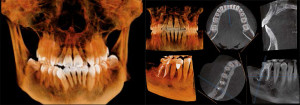

S CB CT slikanjem dobimo zelo natančno tridimenzionalno sliko dela notranjosti glave. CBCT* je najsodobnejša tehnika s področja 3D rentgenske diagnostike. CBCT je hitrejše od običajnega CT slikanja, pacient pa prejme bistveno manjšo dozo sevanja. CBCT omogoča kakovostno diagnostiko in načrtovanje zdravljenja